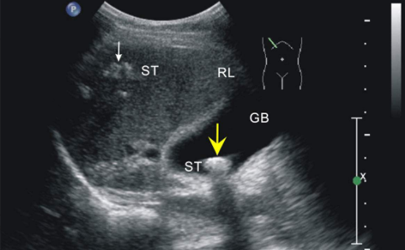

懷孕時需要及時做孕檢,常見的就是B超。B超可以看到寶寶在肚子里的情況,也能看到胎位。正常的胎位是頭位,也就是頭下臀上,如果是臀下頭上就是臀位,也就是胎位不正。那么七個月臀位還能不能糾正呢?..(817)人閱讀時間:2026-01-14

胎兒小是因為吃鈣片嗎 八個月胎兒小怎么辦

孕36周胎兒顯示頭偏小怎么辦 羊水少了吃什么可以補